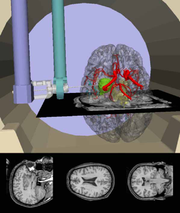

Robot.png

(

file

)

354 KB

1